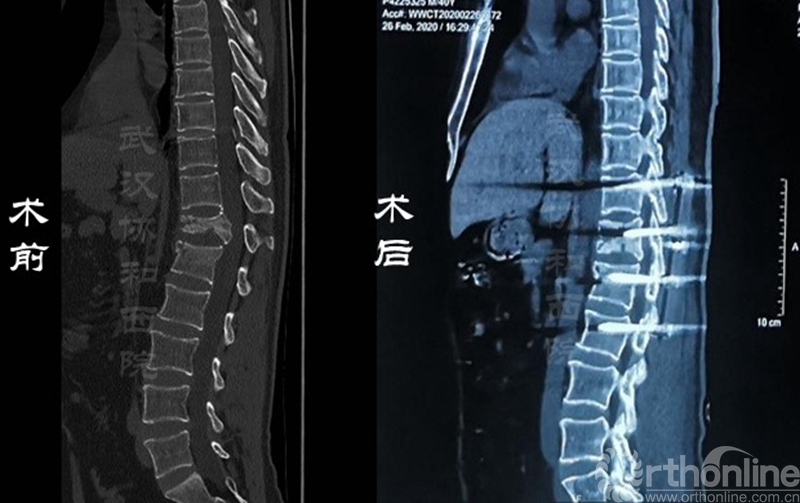

影像学资料对比

其次,患者的脊柱骨折、截瘫和双下肢疼痛的症状明显好转,双下肢感觉功能基本恢复,双侧髋关节、膝关节和踝关节肌力从术前的不到2级恢复到4级,目前患者在助步器辅助下已经逐步开始行走,整体治疗效果达到了预期。